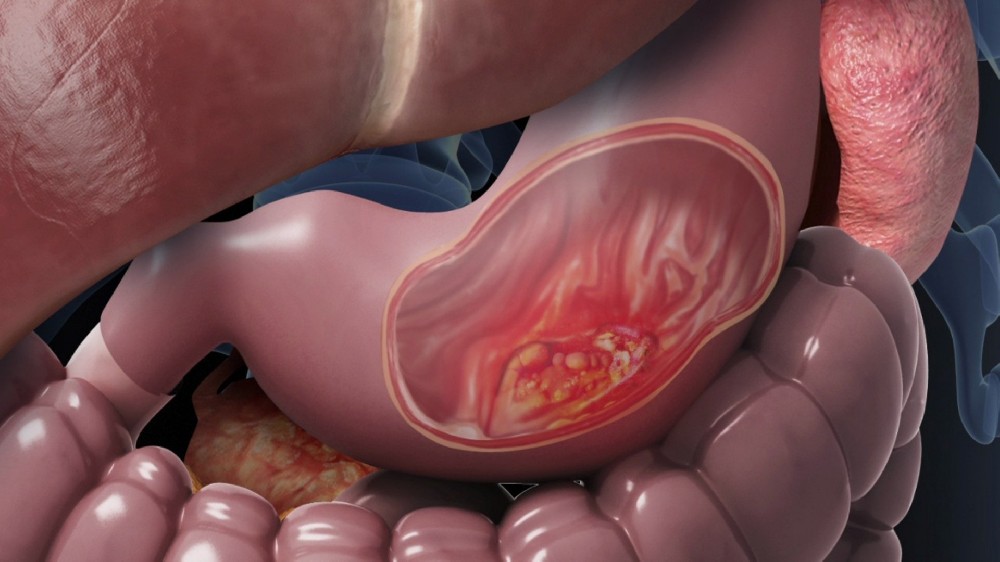

美國代謝腫瘤研究所(AICM)由李國華博士創立的世界級醫療機構,以諾貝爾獎得主Otto Warburg的 "癌細胞能量代謝學說" 爲基石,首創顛覆性 "四位一體靶向代謝療法":通過代謝重編程斬斷腫瘤能量鏈+ 節拍控瘤封鎖轉移路徑 + 基因靶向清除突變根源 + 免疫調節構築終身防禦,徹底改寫癌症治療規則!該療法已登陸美國希望之城、MD安德森癌症中心、凱特琳癌症中心等全球頂級機構,並依託香港代謝腫瘤中心及前海泰康醫院建立亞洲核心基地,專爲中晚期/難治性癌症患者提供趨近零副作用的創新性治療,實現癌痛癌疲乏突破性緩解及生存週期的治癒級延長,讓複雜病例重獲生命掌控權!